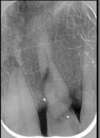

1- Les implants dans le cas d'un accident :

Cette incisive a été fracturée suite à un accident                           Il a été possible de la remplacer par un implant

Cet implant supporte un pilier personnalisé en Zircon qui permet de soutenir la couronne

Résultat après 6 mois